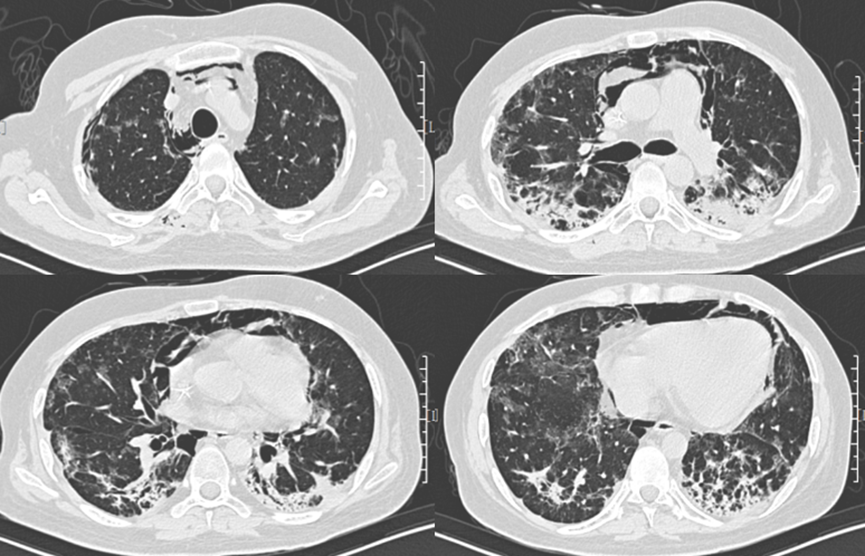

• 胸部CT:双肺磨玻璃样改变(图1)

图1  患者胸部CT(2018年9月13日)

胸部高分辨率CT(high-resolusion computed tomography,HRCT)检查是诊断PJP的重要手段,早期典型的胸部HRCT表现为双肺由中心向外周分布的对称性多发的弥漫性粟粒状、斑点状阴影,边界清晰。炎症急性期HRCT可见以肺门为中心的双侧对称向外分布的弥漫性磨玻璃影,胸膜下较少受累及,呈典型的月弓征表现。恢复期伴随组织修复,纤维结缔组织增生,HRCT呈间质纤维化改变,双肺下叶间隔明显增厚,条索影、网格影等改变。其中肺气囊是PCP较常见的影像学表现,表现为磨玻璃影、间质病变中的薄壁空腔,破裂可引起自发性气胸、纵膈及皮下气肿,少见表现包括有结节、实变、纵隔淋巴结肿大、胸腔积液等。合并其他病原菌感染或有肺部基础疾病者,影像学表现不典型。